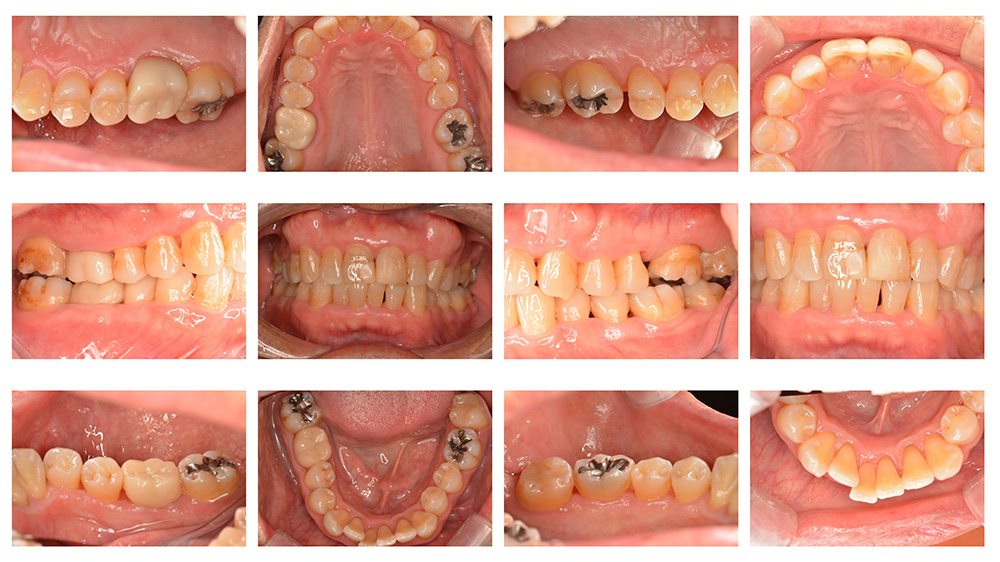

世代・性別

60代男性

主訴

歯ブラシで出血するので見てほしい

治療内容

ブラッシング指導、歯周基本治療、虫歯治療、根管治療、補綴治療

治療期間

6ヶ月

治療費

保険適応内

治療のリスク

治療後にしみる・痛みが出ることがある